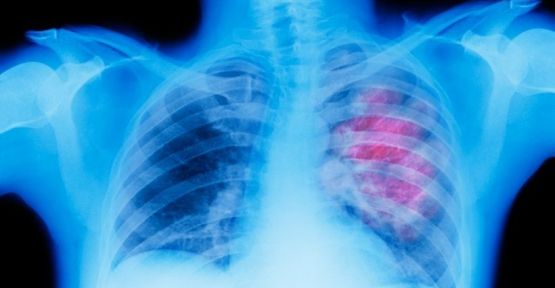

Akciğer kanseri olan hastaların ilaç parası için 'sigara içmemiş' olma şartı!

SGK, akciğer kanseri olan hastaların ilaç parasını ödemek için ‘hiç sigara kullanmamış’ olmasını şart koşuyor.

SGK, akciğer kanseri olan hastaların ilaç parasını ödemek için ‘hiç sigara kullanmamış’ olmasını şart koşuyor. 3 Şubat’tan itibaren geçerli olan tebliğ hakkında konuşan Tüm Eczacı İşverenler Sendikası (TEİS) Genel Başkanı Nurten Saydan, SGK’nin akciğer kanseri, MS, lösemi gibi hastalıklarda getirdiği geri ödeme şartlarının vatandaş sağlığını kötü etkilediğini belirterek, “Bu durum kabul edilebilir değil” dedi.

Tüm Eczacı İşverenler Sendikası (TEİS) Genel Başkanı Nurten Saydan, SGK’nin bazı hastalıklarda getirdiği geri ödeme şartlarının vatandaş sağlığını kötü etkilediğini belirterek, “Örneğin 3 Şubat günü akciğer kanseri olan bir hastanın ilacını ödemek için sigara içmemiş olma şartı getirildi. Bu durum kabul edilebilir değil” dedi.

MS HASTALARI DA ZORDA

Hastaların hayatlarını tehdit eden bu uygulama SGK ve Sağlık Bakanlığı tarafından derhal düzeltilmeli. Akciğer kanseri, MS, Lösemi gibi birçok hastalıkla mücadele eden hasta bu uygulamayla hayati riskle karşı karşıya kalma tehlikesinde kalıyor. Akciğer kanserinde kullanılan Erlotinib etken maddeli ilaç için SGK, vatandaşın ‘hiç sigara kullanmamış’ olmasını şart koşması ve daha önce sigara kullanmış olan kişilerin tedavisi için bu ilacın parasını ödememesi, Multipl skleroz (MS) hastalarında kullanılan Fingolimod etken maddeli ilacın ödenmesi için başka bir ilacın bir yıl süreyle kullanılmasını şart koşması, Azasitidin etken maddeli ilacın kronik miyelomonositer lösemi (KMML) ve akut miyeloid lösemi (AML) tedavisinde başarılı olsa bile 6 kürden fazla ödenmemesi, krizotinib etken maddesi içeren küçük hücreli dışı akciğer kanseri tedavisinde kullanılan bir ilacın en az bir seri kemoterapi kullanmamış hastalara doktor gerekli görse bile ödenmemesi dikkat çekici birkaç örnek. Yani SGK daha önce sigara içti diye bir hastayı akciğer kanseri tedavisine uygun görmediği gibi, MS hastalığı olan bir hastanın başka bir ilaçla bir yıl zaman kaybetmesini şart koşarak adeta hastanın daha ağır ve gecikmiş bir MS hastalığıyla karşı karşıya kalmasını göze alabiliyor. “